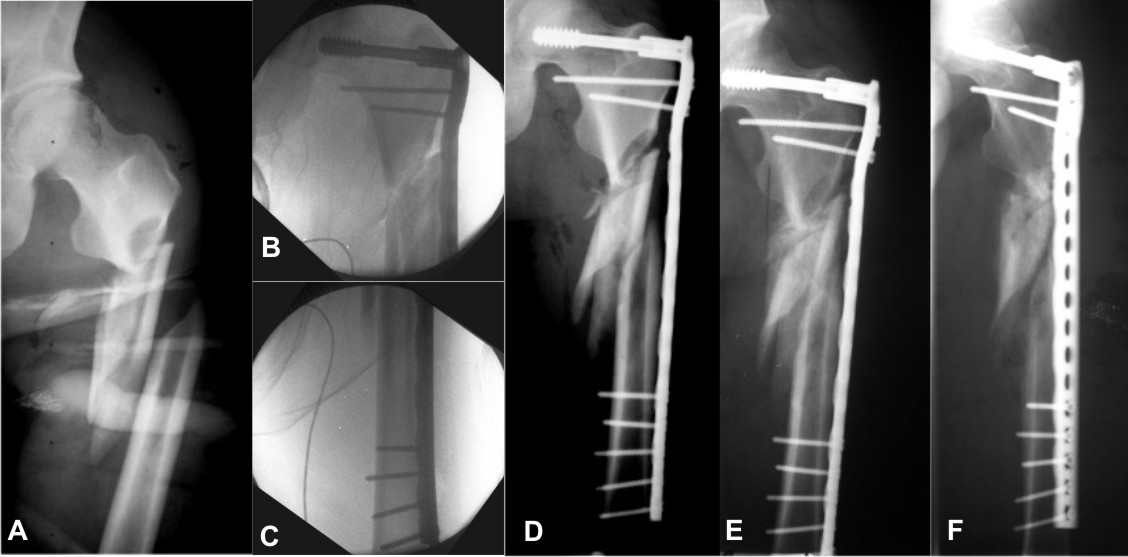

Переломы дистального отдела плечевой кости (локтя) возникают в результате падения на локоть с согнутой рукой.Выделяют две основные группы: те, которые затрагивают поверхность сустава (внутрисуставные переломы), и те, которые не затрагивают поверхность сустава (внесуставные переломы). Кроме того, лечение этих переломов у детей отличается от лечения у взрослых. В большинстве случаев эти переломы нестабильны и требуют какой-либо внутренней фиксации, чтобы предотвратить их заживление в плохом положении.

Надмыщелковые переломы плечевой кости часто встречаются у детей и обычно возникают в результате падения с обезьяньих брусьев.В отличие от переломов у взрослых, это обычно гиперпространственная травма. Обычно наблюдается явная деформация руки с быстрым отеком. Лечение включает выравнивание костей под рентгеновским снимком (рентгеноскопия) и удерживание их на месте с помощью булавок, вводимых через кожу (чрескожно) в кость. В редких случаях для визуализации перелома необходим разрез. Большинство детей остаются в больнице на ночь и выписываются на следующий день. Спицы обычно удаляются в клинике через 4 недели, а гипсовая повязка полностью снимается примерно через 6 недель.Хотя дети, как правило, немного беспокоятся о том, чтобы удалить штифты, это практически безболезненно и не гарантирует риска дополнительной анестезии.

Переломы дистального отдела плечевой кости у взрослых обычно требуют хирургического вмешательства. Небольшой процент этих переломов можно вылечить с помощью гипсовой повязки на руку. Однако длительная иммобилизация локтя приводит к значительной и длительной скованности сустава. Эти переломы обычно затрагивают поверхность сустава (хрящ). Обычно поверхность сустава гладкая, что позволяет костям скользить друг относительно друга с очень небольшим трением.Если поверхность неконгруэнтна, потому что кости не выровнены, происходит хроническое повреждение сустава, что в конечном итоге приводит к артриту. Очень важно убедиться, что поверхность хряща восстанавливается как можно точнее. Операция рекомендуется при смещении поверхности сустава на 2 мм или более.

Хирургия включает повторное выравнивание перелома и проведение ремонта пластинами и винтами. Операция длится около 2 часов, и большинство пациентов остаются в больнице на ночь.Наиболее частыми осложнениями операции являются инфекция (около 2%), ригидность (10%) и повреждение нервов, называемое нейропраксией (около 2-3%). Нейропраксия — это состояние, при котором нерв ((локтевой нерв)), проходящий вдоль задней части локтя (забавная кость), раздражается и не работает должным образом после операции. В большинстве случаев это временно, но на устранение может уйти несколько месяцев. После хирургического вмешательства пациенты могут начать двигать рукой в течение 2 недель после операции, и риск долговременной скованности уменьшается.